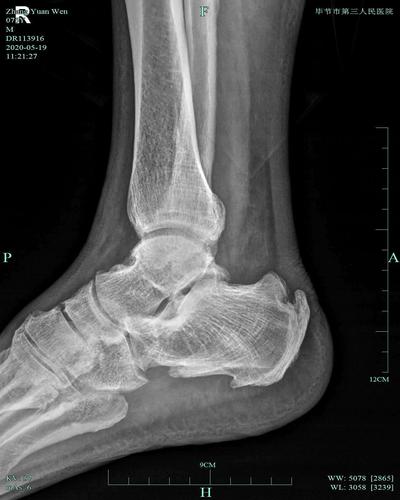

儿童踝关节正常x片